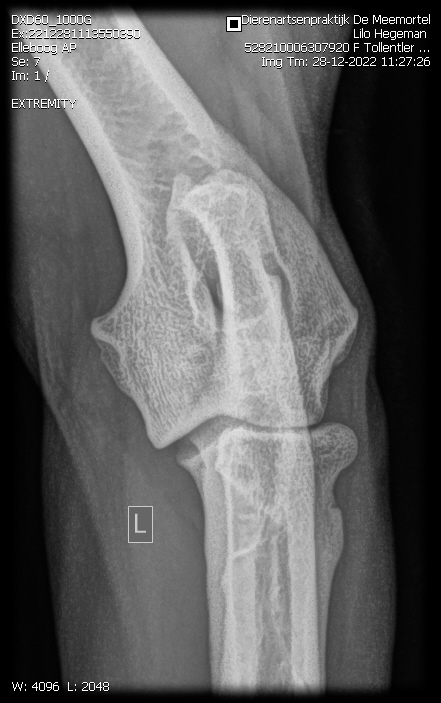

Eerste Gezondheidsresltaten Tollentler

Lilo onze eerstgeborene Tollentler in de kleur Tan is inmiddels volledig getest.

Zo ook het overige. Zie onderstaand.